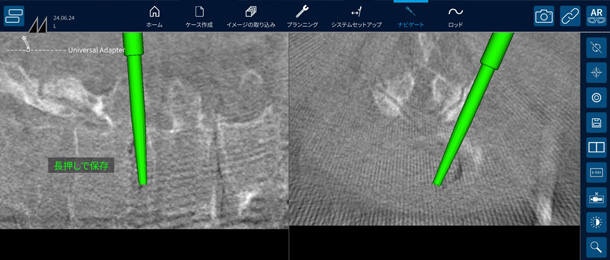

手術ナビゲーションシステムとは

せぼねの手術で用いられるナビゲーションシステムは、手術を安全に行うための機器になります。せぼねの病気はさまざまあり、患者さんによって病気の部位や骨の変形は異なります。また、せぼねの周りには大事な神経組織や血管が位置しているため、これらを傷つけないように手術が行われる必要があります。これまでは透視装置などを駆使して手術が行われていました。しかし、固定術で施行されるスクリューの誤設置や固定材料の不適切な設置がなされる場合がありました。

当院では様々な種類のナビゲーションシステムを採用しています。そのため、手術はより安全に行われ、手術時間の短縮、出血量の低減、被爆量の減少、さらには早期復帰につながるものと考えています。

ナビゲーションシステムを用いた

内視鏡手術

ナビゲーションシステムを用いた内視鏡手術

スクリューを用いた手術

ナビゲーションシステムを用いたスクリューを用いた手術